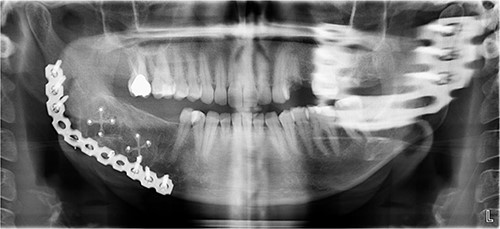

A 40-year-old woman presented with swelling on the right side of her mandible. She had completed orthodontic treatment 2 years earlier. A panoramic radiograph showed a unilocular radiolucency extending from the mandibular angle to the right first molar region (Figs 1–3).

Panoramic radiograph showing a unilocular radiolucency extending from the right mandibular angle to the right first molar region.

Panoramic radiograph highlighting the extent of the lesion from the mandibular angle to tooth #46.

The excised specimen’s histopathology confirmed its benign nature. One year postoperatively, the patient showed no infection or inflammation, with optimal mouth opening and mandibular movement. The reconstruction plate remained stable and intact (Figs 6 and 7).

Postoperative panoramic radiograph demonstrating the reconstruction plate in place after tumor resection and bone grafting.

Follow-up panoramic radiograph showing stable reconstruction plate and no signs of recurrence one year postoperatively.